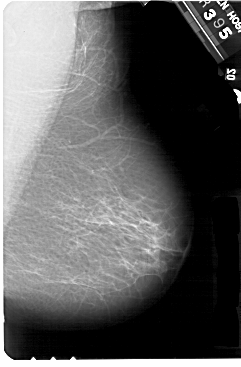

A_1266_1.LEFT_MLO

LEFT_MLO LINES 5491 PIXELS_PER_LINE 3586 BITS_PER_PIXEL 12 RESOLUTION 43.5 OVERLAY